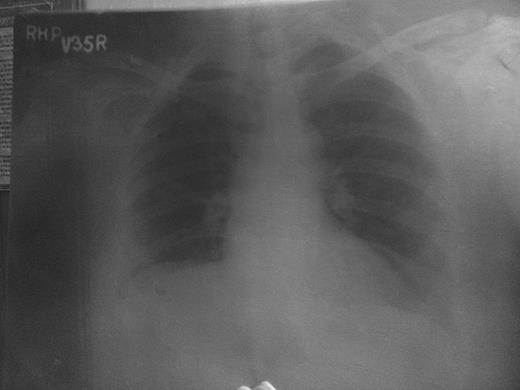

Clinical examination revealed an ulcerative lesion 3 × 2.5 × 2.5 cm in the right clavicle at the junction of medial two-third and lateral one-third of the clavicle, with irregular margins, firm base and foul-smelling discharge. Bone was seen exposed with sequestrum present (Fig. 1). There was no evidence of cervical or axillary lymphadenopathy and the lung fields were essentially clear. Routine investigations showed moderate hypochromic microcytic anaemia, haemoglobin 9 g/dl, total leukocyte count of 7900 with polymorphs 42%, lymphocytes 54% and eosinophil 4%. Renal and hepatic panels were within normal limit. ESR was 35 mm. The gram staining of the discharge from the ulcer revealed gram-positive cocci, and the Ziehl Nielsen staining for acid-fast bacilli was negative. Culture of the discharge revealed growth of Staphylococcus aureus. ELISA IgG/IgM for TB was negative. HIV-I and II were negative. Chest X-ray was grossly normal (Fig. 2). Sequestrectomy was done and the bone along with the excised tissue was sent for biopsy. Histopathology showed it to be either foreign body granuloma or rare possibility of tubercular pathology.